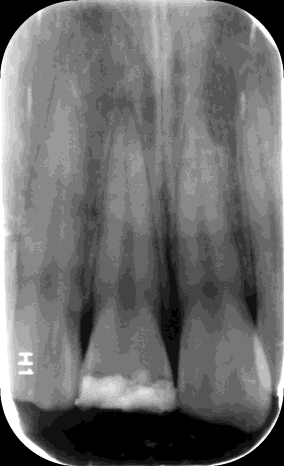

检查:#11 牙冠折断约1/3,见露髓孔,孔径大于2mm,叩(+-),松(I°),电测有活力,牙龈稍红肿,伴出血 X线示:#11冠部折断,根尖未见明显阴影

诊断:#11冠折(露髓) 治疗:#11碧兰麻下开髓,清理髓腔及根管,双氧水和生理盐水交替冲洗,测WL,拍片试尖达工作长度,根管内导入糊剂,侧压充填中下段,热牙胶充填上段,X线示恰填,ZOE暂封。